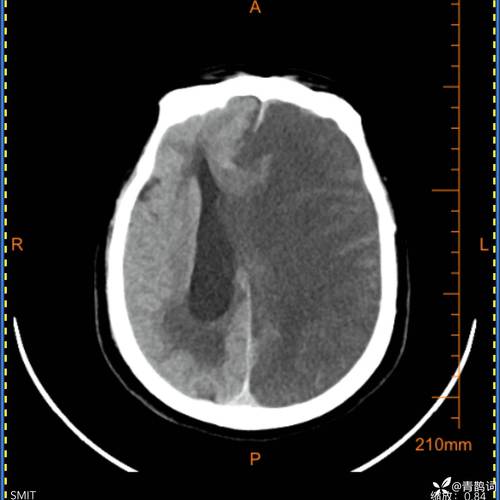

B. 中线结构 (Midline Structures)

- 通俗理解:想象一下我们的大脑,有一个“中央分割线”,把大脑分成了左、右两半,这条“线”以及它周围的一些关键结构,就叫做“中线结构”。

- 医学结构:这包括大脑镰(像一块帘子,分隔左右大脑半球)、第三脑室、松果体等,这些结构位于大脑的正中央,左右两侧的压力应该是对称的。

- 通俗理解:原本在正中央的“中线结构”,现在被推向了左边。

- 深层含义:这说明右侧大脑的压力,比左侧大脑的压力要大得多,就像一个气球,如果一边被用力挤压,中间的隔膜就会被推向另一侧。

- 中线被挤压:右侧巨大的压力,像推土机一样,把位于正中央的“中线结构”(大脑镰等)硬生生地推向了压力较小的左侧。

- 常见类型:如果中线向左移位,最容易发生的是颞叶钩回疝(Uncal Herniation),即颞叶的海马钩回部分被挤入小脑幕裂孔,压迫动眼神经和脑干。